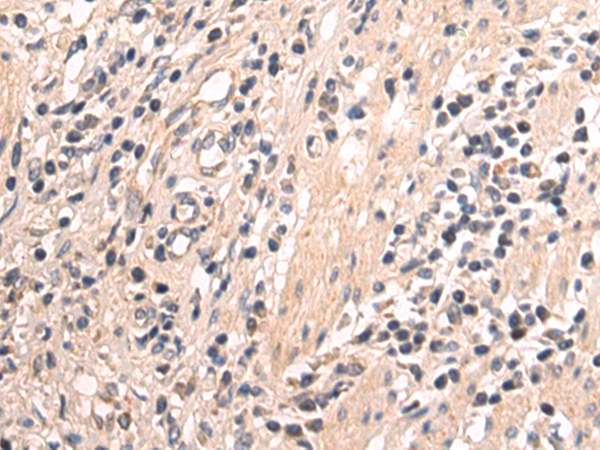

分类: 科研抗体货号: P10708别名: ASH1; HASH1; MASH1; bHLHa46应用: IHC反应种属: Human, Mouse, Rat